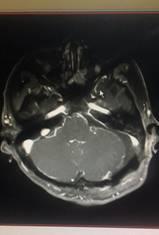

术前 术后

患者术后恢复

经过两位主刀医师和医疗团队的艰苦奋战,两名患者手术成功,目前病情已稳定,无明显的面瘫加重等表现。